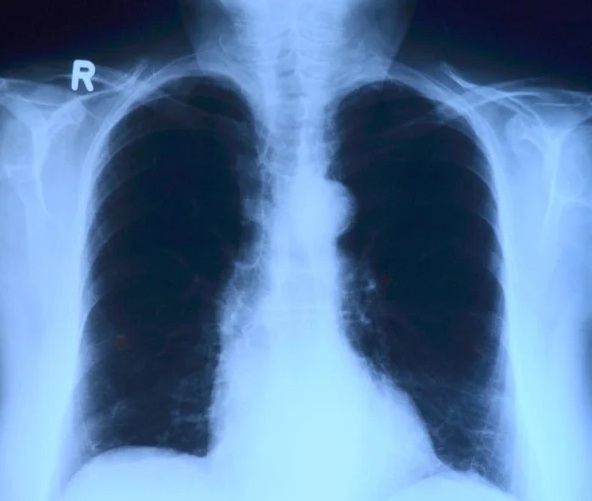

Если у человека на этом практически бессимптомном этапе выявлен туберкулез, мы можем быстро его пролечить и вернуть в строй, а если уже проявились симптомы, тем более дошло до таких тревожных, как кровохарканье, то речь идет об открытой форме. Чем дольше он не попадет к нам, тем опаснее для него и окружающих. Поэтому флюорографию нужно делать согласно нормам СанПиН раз в два года, а я бы посоветовала раз в год, хотя бы для собственного спокойствия.